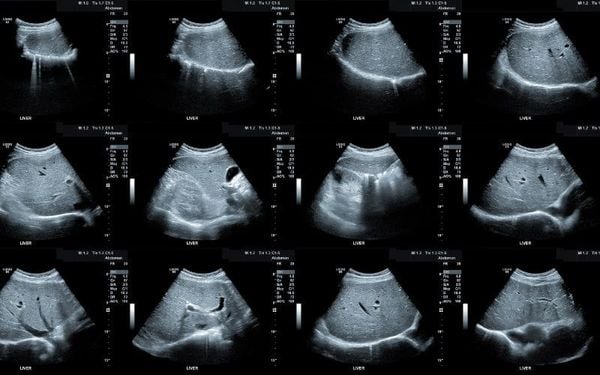

Siêu âm gan – Bản đồ sức khỏe gan trong tầm mắt

Siêu âm gan là một trong những phương pháp chẩn đoán hình ảnh phổ biến, không xâm lấn, cho phép bác sĩ quan sát hình dạng, mật độ và kết cấu của gan. Tuy nhiên, với người bình thường, việc hiểu các thuật ngữ như “tăng âm”, “giảm âm”, “gan thô” không hề đơn giản.

Thực tế, những kết quả này không hẳn luôn chỉ ra bệnh lý cụ thể, mà thường là dấu hiệu cảnh báo sớm về tình trạng rối loạn chuyển hóa, gan nhiễm mỡ hoặc viêm nhẹ, chủ yếu xuất phát từ lối sống và dinh dưỡng không lành mạnh.